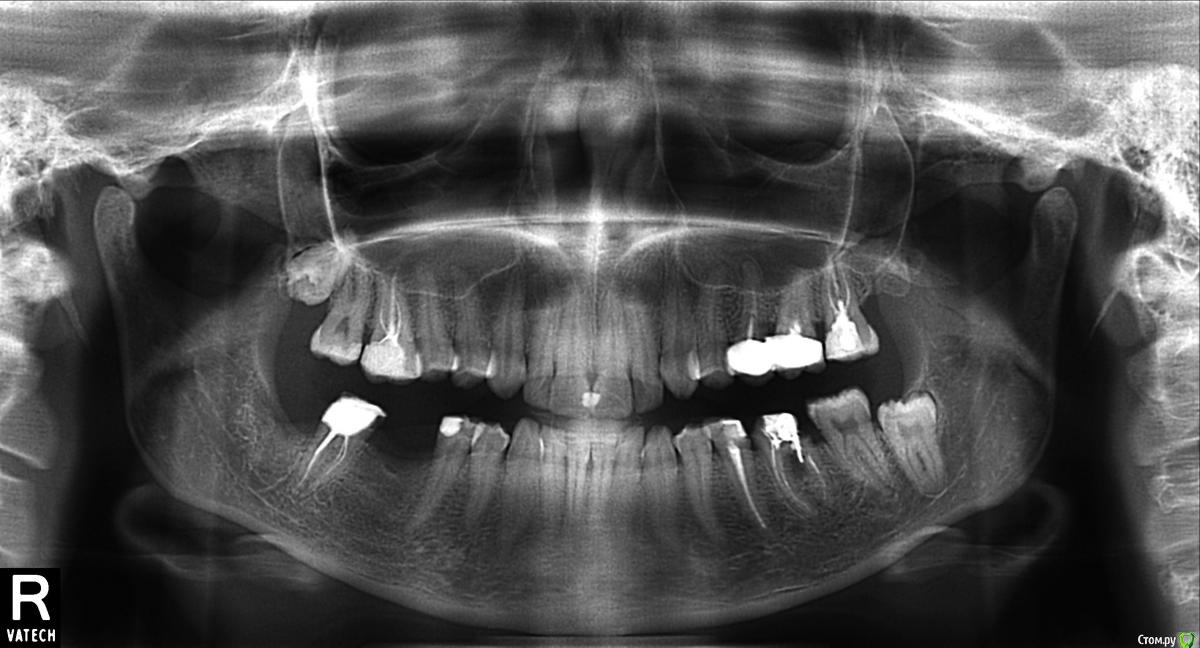

Jonatan Опубликовано 24 февраля, 2015 Поделиться Опубликовано 24 февраля, 2015 Здравствуйте!думала делать имплантацию нижних 6-к, у намеченного имплантолога удалила 8-ку,сама операция прошла легко, полдня ходила со льдом, пила все лекарства,но несмотря ни на что почему-то очень тяжелый период восстановления был(отек с яблоко 3 дня, кетанов 3 недели, боль в десне 2 месяца,остаточные явления - десна болит, но уже скорее всего из-за проблем протезирования 7-ки).В итоге возникло ощущение, что мой организм не перенесет имплантацию и лучше остановиться на варианте двух тройных мостов.Насколько правомерны мои опасения?Может ли имплантация с костной пластикой пройти легче, чем удаление 8-ки?Боюсь, что выйду из строя на полгода... 1 Ссылка на комментарий